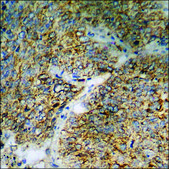

ELISA: 1:5000, immunohistochemistry: 1:50-1:100, western blot: 1:500-1:1000